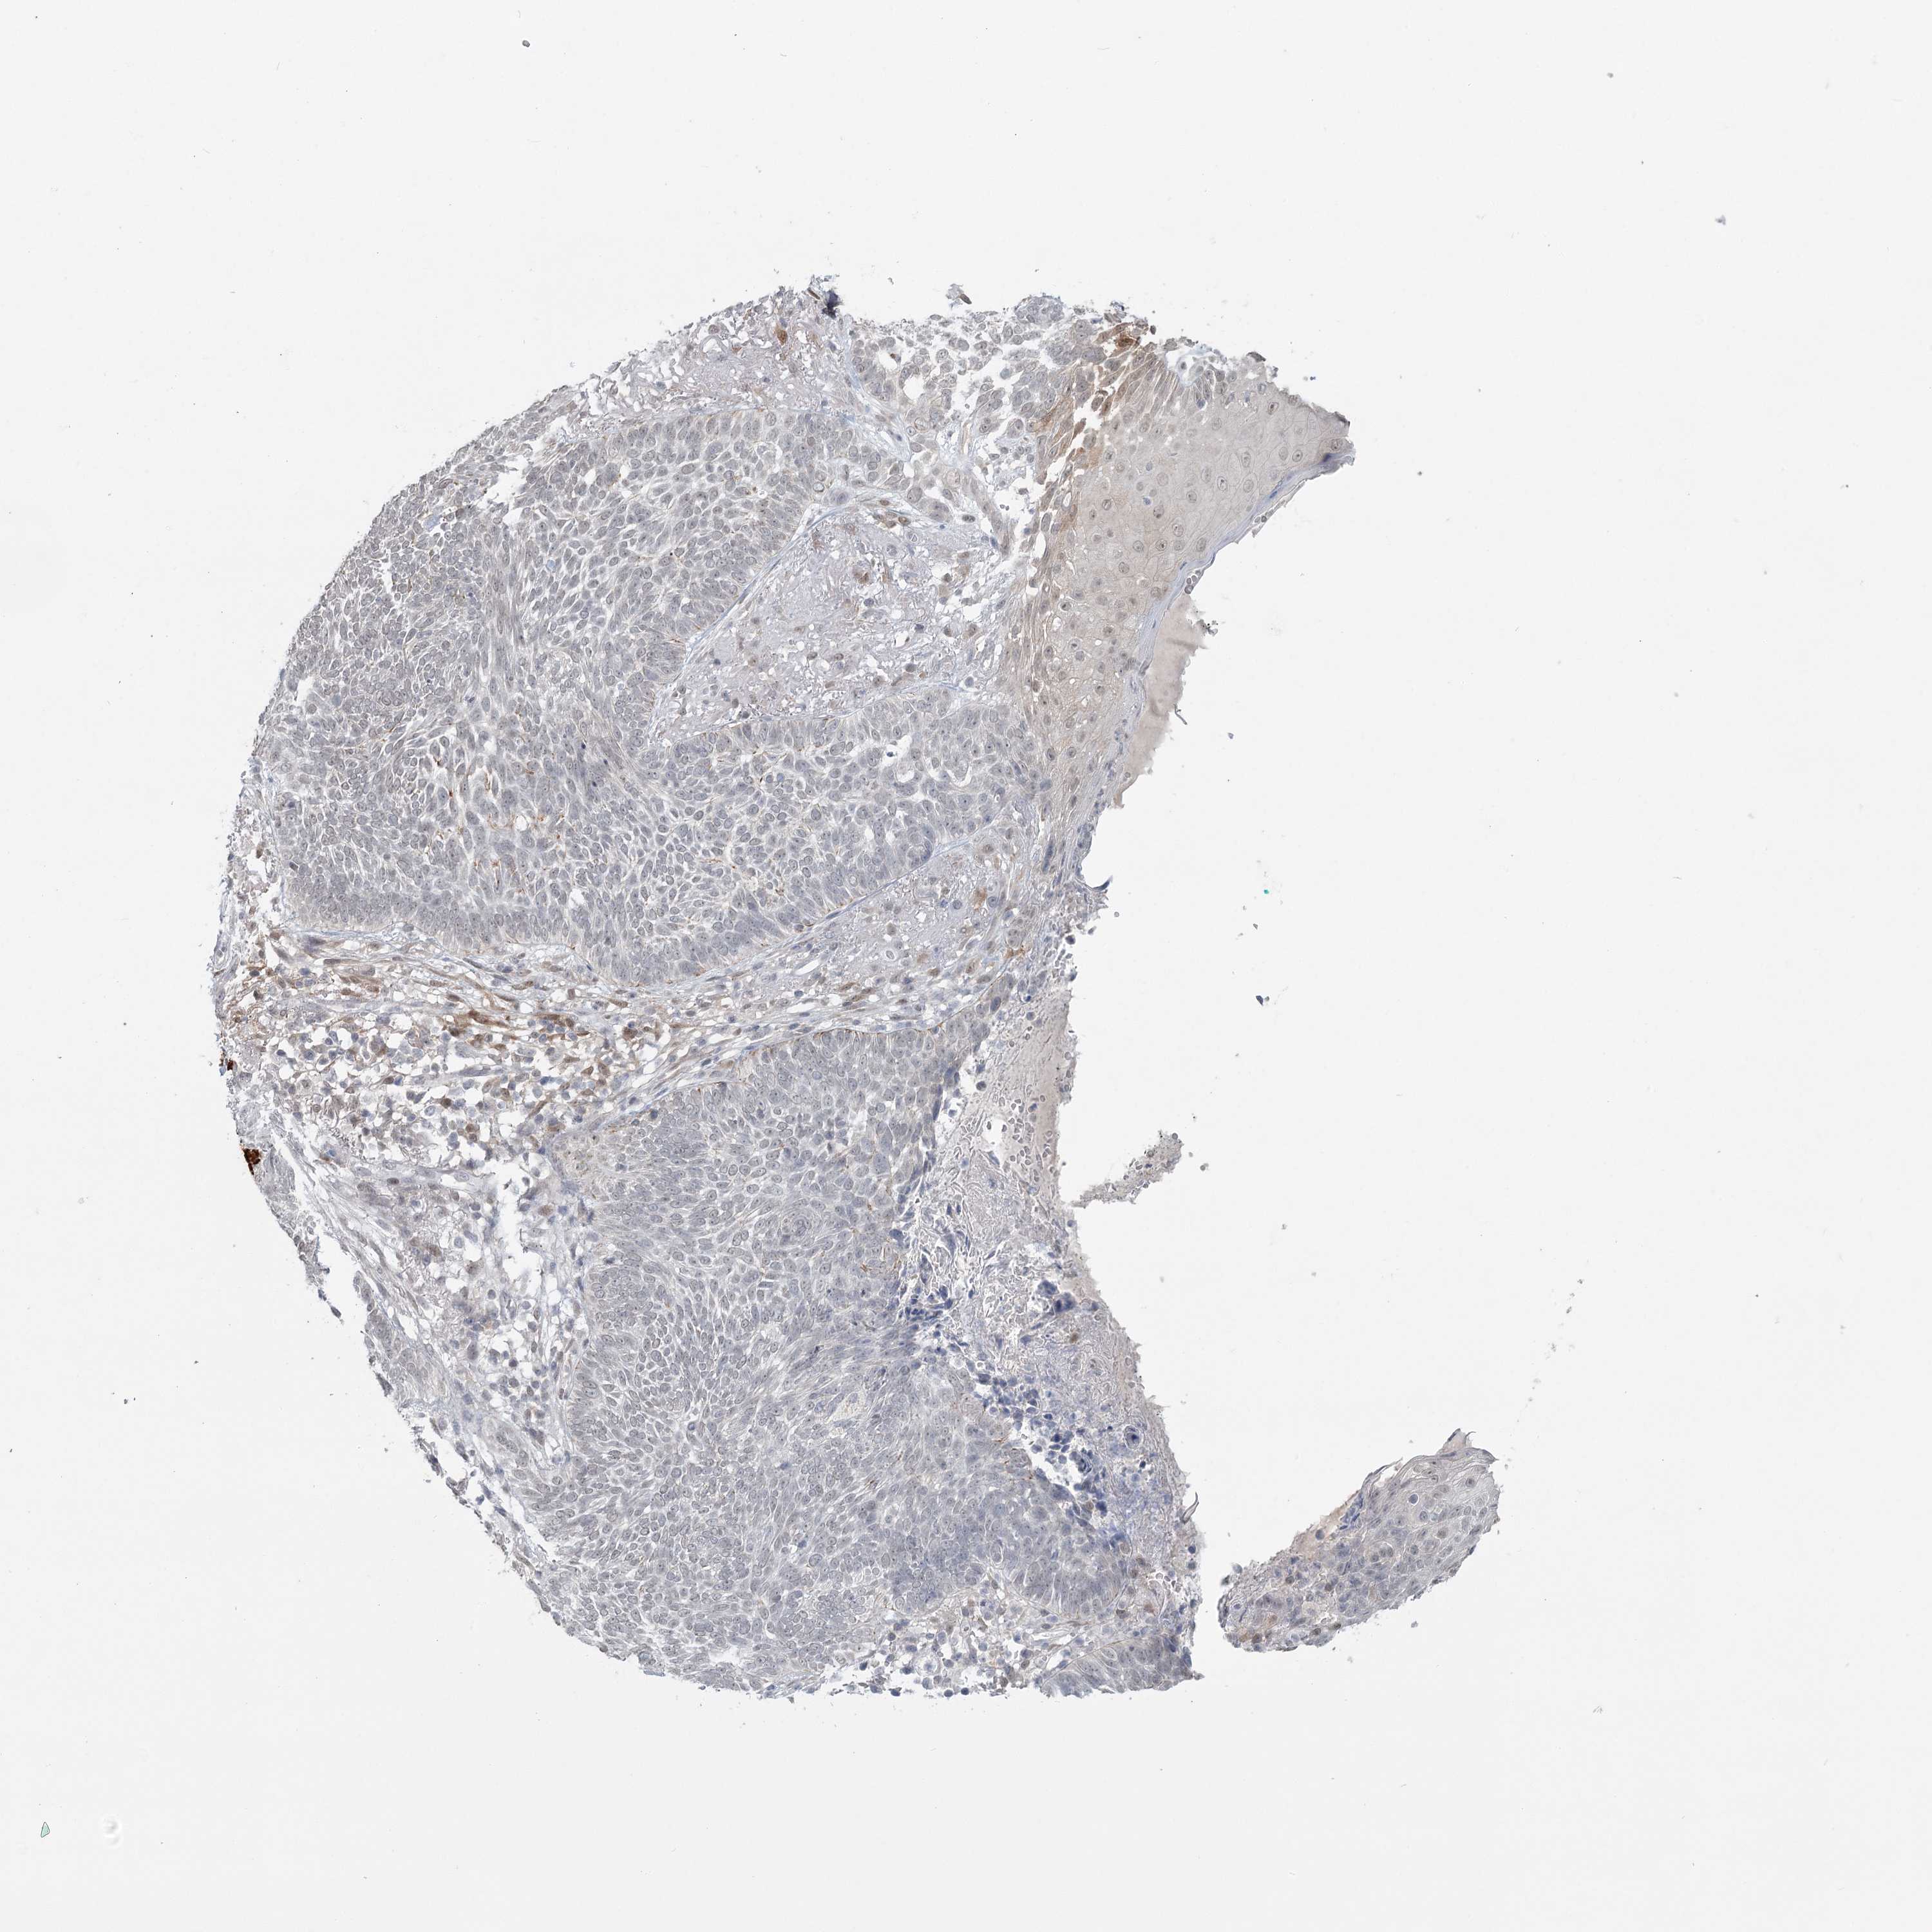

Basal cell and squamous cell cancer

SKIN CANCER - Protein expressioni

A mouse-over function shows sample information and annotation data. Click on an image to view it in a full screen mode. Samples can be filtered based on level of antibody staining by selecting one or several of the following categories: high, medium, low and not detected. The assay and annotation is described here.

Antibody stainingi

Antibody staining in the annotated cell types in the current human tissue is reported as not detected, low, medium, or high, based on conventional immunohistochemistry profiling in selected tissues. This score is based on the combination of the staining intensity and fraction of stained cells.

Each image is clickable and will lead to virtual microscopy that enables deeper exploration of all samples and also displays staining intensity scores, fraction scores and subcellular localization as well as patient and tissue information for each sample.

Antibody HPA023187

Antibody CAB034226

Staining

High

Medium

Low

Not detected

Intensity

Strong

Moderate

Weak

Negative

Quantity

>75%

75%-25%

<25%

None

Location

Nuclear

Cytoplasmic/membranous

Cytoplasmic/membranous,nuclear

Squamous cell carcinoma, NOS

Squamous cell carcinoma, metastatic, NOS